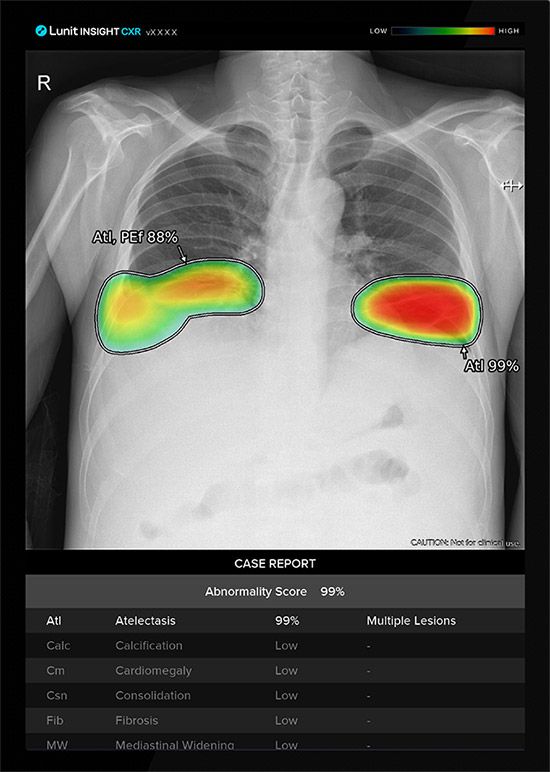

연구팀은 남아프리카공화국에서 2017년 8월부터 2019년 7월까지 2년간 결핵 유병률 조사에 쓰인 774명의 흉부 엑스레이 데이터를 활용해 루닛의 흉부 엑스레이 AI 영상 분석 솔루션 ‘루닛 인사이트 CXR’을 포함한 총 12개 상용 AI 솔루션에 대한 비교 분석을 진행했다.

연구 결과, AI 모델의 대표적 성능평가 지표인 AUC 수치를 기준으로 했을 때, 루닛 인사이트 CXR의 결핵 검출 능력은 0.902로 연구 분석에 활용된 모든 AI 제품 중 가장 높은 수치를 보였다.